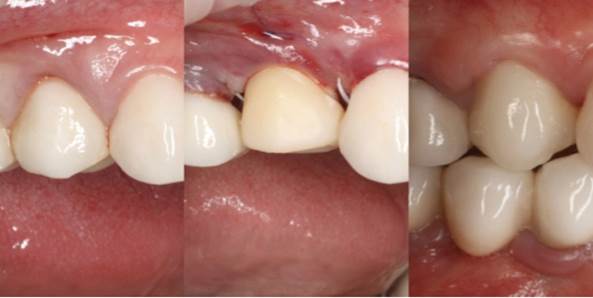

Clinical case: Extraction, immediate implant placement, & provisionalization

- Courtesy of Dr. Iulian Filipov, Romania -

AnyRidge, R2GATE, guided surgery, immediate placement, immediate provisionalization, initial stability, Dr. Iulian Filipov, #25, maxillary posterior, immediate loading, Mega ISQ